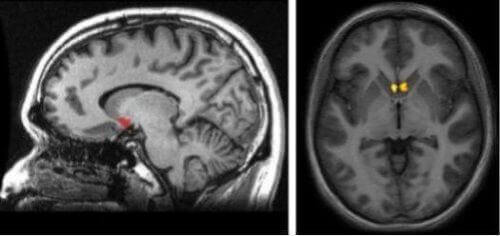

Jądro półleżące leży w miejscu, gdzie łączą się jądro ogoniaste, skorupa i przegroda. To umiejscowienie jest jedną z najważniejszych cech jądra półleżącego, ponieważ oznacza to, że obszar ten znajduje się na drodze, jaką przemieszcza się dopamina. Jest to tak zwany szlak szlak mezolimbiczny. Pojawia się tutaj aktywność za każdym razem, kiedy twój mózg rejestruje, że doświadczasz czegoś przyjemnego lub satysfakcjonującego.